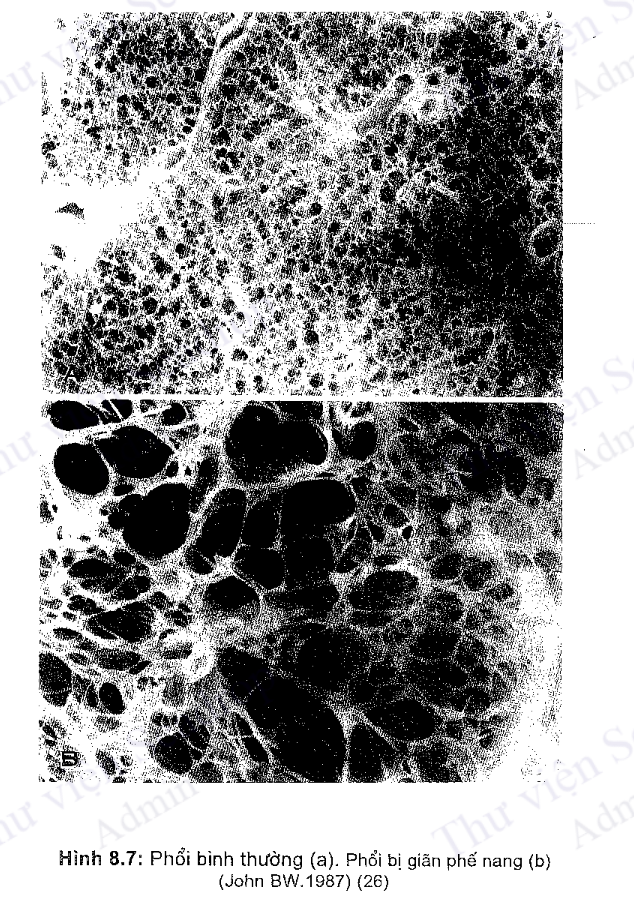

Người ta chia làm 2 loại giãn phế nang: Giãn phế nang ở trung tâm và giãn phế nang toàn bộ (hình 8.6).

Loại giãn phế nang ở trung tâm thường kèm theo giãn các tiểu phế quản hô hấp, các ống phế nang và một số phế nang ở trung tâm. Giãn phế nang toàn bộ thì cả một vùng các phế nang bị giãn, loại này hay gặp khi thiếu hụt alpha ₁ AI.

Về mặt vi thể, khi giãn phế nang sẽ tạo thành nhiều túi khí đường kính có thể đến 1cm, thậm chỉ còn lớn hơn. Ở những vùng phổi bị giãn phế nang, khả năng khuếch tán khí qua thành phế nang bị giảm, thể tích cặn của phổi tăng lên do một lượng khí chứa trong các phế nang bị giãn không tham gia hô hấp.